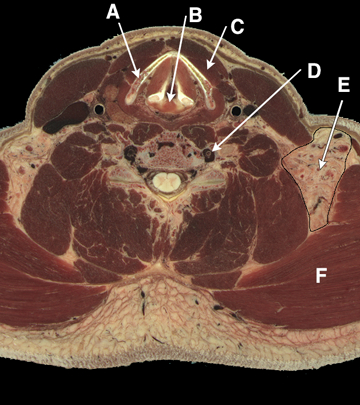

Neck structures, high resolution

Answers